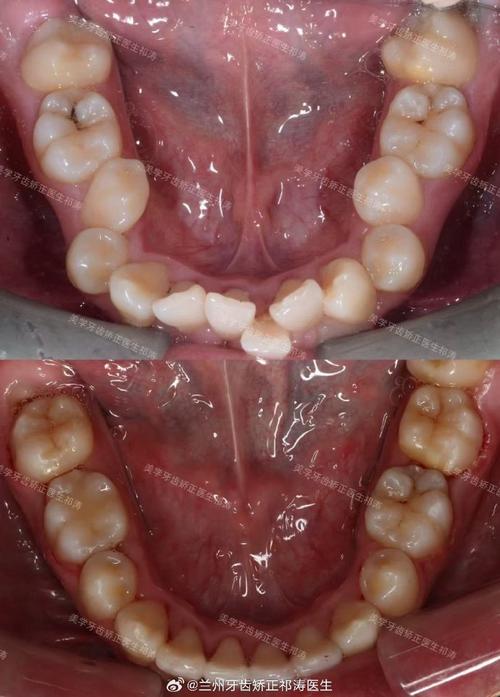

拔牙是矫正中常见的手段,主要用于解除牙列拥挤、调整牙齿位置或为前牙内收创造空间,拔牙后,原本拥挤的牙齿需要向拔牙间隙移动,这一移动过程必然伴随牙齿的松动,拔除第一前磨牙后,尖牙和后牙需向拔牙隙移动,移动初期牙齿会有轻微“晃动感”,这是牙周膜改建的正常表现,通常在1-2周内逐渐缓解。